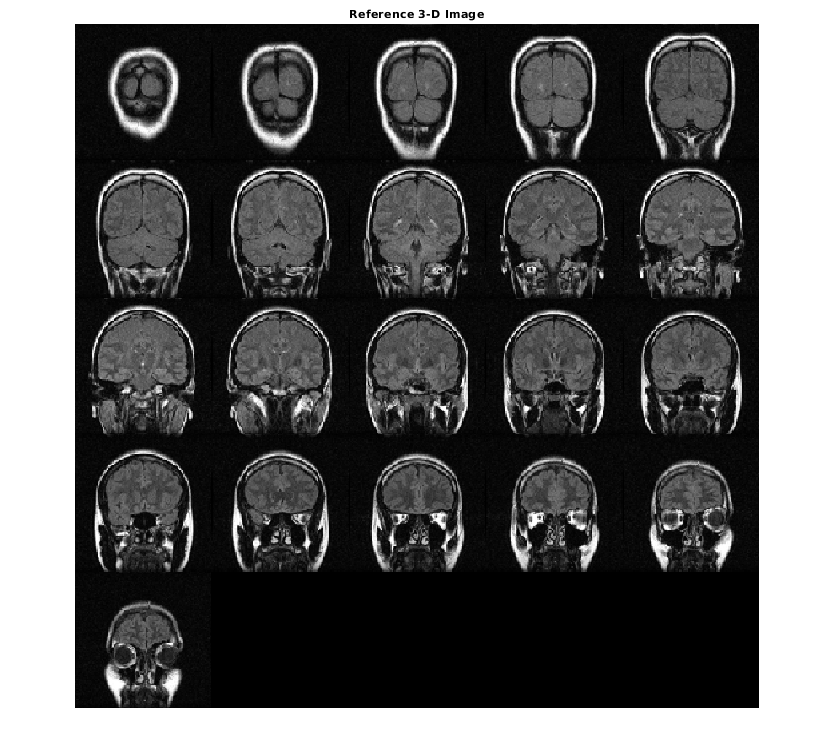

Измените ссылку как стек полутоновых срезов для отображения.

ref = reshape(mristack,[256,256,1,21]);

Отобразите ссылочный объем как срезы. Чтобы отобразиться правильно на экране, ссылочный объем уменьшается на коэффициент 0,5 использований imresize.

ref_downsized = imresize(ref,0.5);

figure

montage(ref_downsized,'DisplayRange',[])

title('Reference 3-D Image')